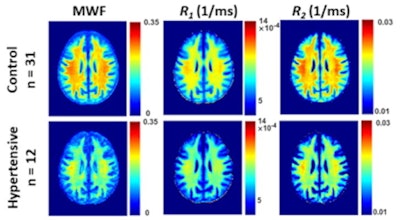

The study included 90 individuals; of these, 30% had high blood pressure, 3.3% were diabetic, and 33.3% were smokers. All underwent an MRI exam that used a BMC-mcDESPOT protocol (which consists of both short and long T1 and T2 components); their blood pressure was also tracked three times in a seated position, with hypertension defined as readings higher than 140/90. The researchers generated whole-brain maps, focusing on 14 white matter regions of interest.

They reported significant associations between high blood pressure and relaxometry and DTI metrics in a number of white-matter brain regions.

"Specifically, we found negative regional correlations between hypertension and MWF [myelin water fraction], a specific and direct measure of myelin content, with hypertensive subjects exhibiting significantly lower values of MWF," the group noted.